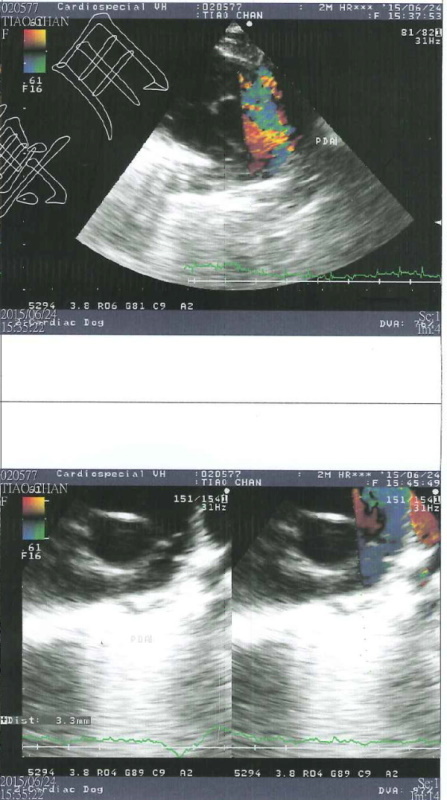

而幸運長大的三隻小奶貓分別取名貂蟬、圓圓、西施,而六月天氣變化大,早上大太陽夜裡又滂沱大雨,小貓們出現鼻氣管炎的現象,張口呼吸感覺很不舒服,貂蟬由其嚴重,呼吸得很用力非常倦怠,緊急送往醫院檢查,醫師懷疑可能有心臟方面的疾病,建議轉診道心臟專科"專心動物醫院"進行心臟超音波檢查,檢查結果心跳超快已有肺氣腫情況,診斷為PDA(開放性動脈導管),開放性動脈導管是一種常見天生的心臟狀況,在母體中血流的需求與出生後不同,而在主動脈與肺動脈之間有一條相通的血管,稱為動脈導管,通常這條血管會在出生後兩三天之內關閉,而貂蟬出生之後動脈導管沒有關閉,導致血流會從大動脈轉而流向肺動脈,一般會有易倦、生長停滯、咳嗽、呼吸速率增加、喘息等等狀況,而此次鼻氣管炎使得狀況更加明顯危急,目前貂蟬住在氧氣室內,這種先天性心臟病可透過手術治療,但需至少體重要到達2公斤才可手術,6/18~6/25狀況嚴重住養氣室費用較高,6/26離氧後觀察三天情況穩定,已帶回安養之家照顧,需定期回診,醫療費用還請各位幫忙。動物近況說明: 住院醫療費用26748